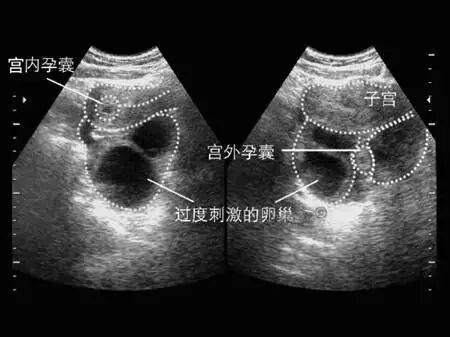

宫外孕是一种相当危险的疾病,据统计由大约2%的女性会遇到宫外孕的情况,号称女性“隐形杀手”。宫外孕发生主要与输卵管畅通程度有关,一旦被诊断为宫外孕,应立即送医院救治。宫外孕破裂出血后,应立即输血,并进行剖宫手术。